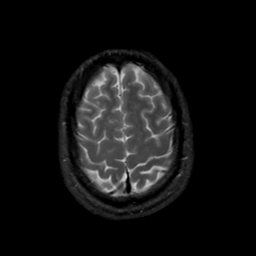

MR Study #20 October 6, 1991 -- Slice #42